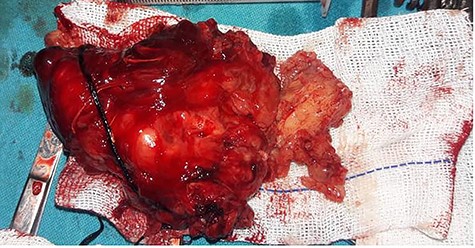

After obtaining the patient’s informed consent, surgery was planned to approach the deeper lobe of parotid gland and para-pharyngeal mass by transparotid, transmandibular swing approach in order to achieve radical excision of the mass. Superficial parotidectomy was done to preserve the facial nerve. After exposure of the parasymphysis, body and ramus of the mandible, mandibular swing access osteotomy was planned. The osteotomy cuts were planned by preserving the inferior alveolar neurovascular bundle, and the media surface of the mandible was exposed to visualize parapharyngeal structures. The facial nerve branches around the tumor were dissected out past the mass, so that the tumor could be peeled away from the facial nerve (Fig. 2). It was completely excised in toto. The measurements of the tumor were 16 × 10 × 4.5 cm in size (Fig. 3). Histopathological examination revealed the features suggestive of pleomorphic adenoma. The patient was discharged after 9 days with no facial nerve deficit.

Gross feature of the mass Showing excised specimen of 16 × 10 × 4.5 cm in size